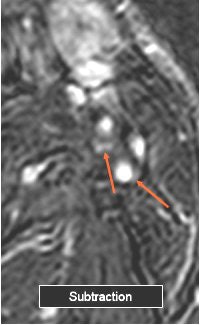

Electronic subtraction (unenhanced minus enhanced axial images) was performed. Internal carotid stenoses were graded on maximum intensity projection (MIP) and multiplanar reformatted (MPR) coronal images. North American Symptomatic Carotid Endarterectomy Trial (NASCET) criteria were applied to judge the percentage of stenosis.

Plaque enhancement was evaluated on axial images by two radiologists in consensus on a four-point scale (0 equaled no enhancement; 3 equaled clear enhancement). They looked at enhanced, unenhanced, and electronic subtraction images.

The results showed that in 92 carotids mild stenosis was found in 29 segments (NASCET 32%), moderate stenosis in 39 (42%), and severe stenosis in 24 (26%). Plaque enhancement was detected in eight of 46 patients and in nine of 92 carotids. The degree of stenosis in these cases was mild (22%), moderate (67%), and severe (11%).

The mean score for plaque enhancement on unenhanced and enhanced images was 1.44. On subtracted images, the mean score was 2.44.

![]() |

| Above, the unenhanced image. Below, the enhanced image and the MRA showing plaque enhancement, which is more evident after electronic subtraction. All images courtesy of Dr. Francesco Sardanelli. |

"We can say that subtraction imaging is a useful tool to detect plaque enhancement," Flor said. "Plaque enhancement does not seem to correlate with the degree of stenosis as we see a large prevalence of moderate stenosis."